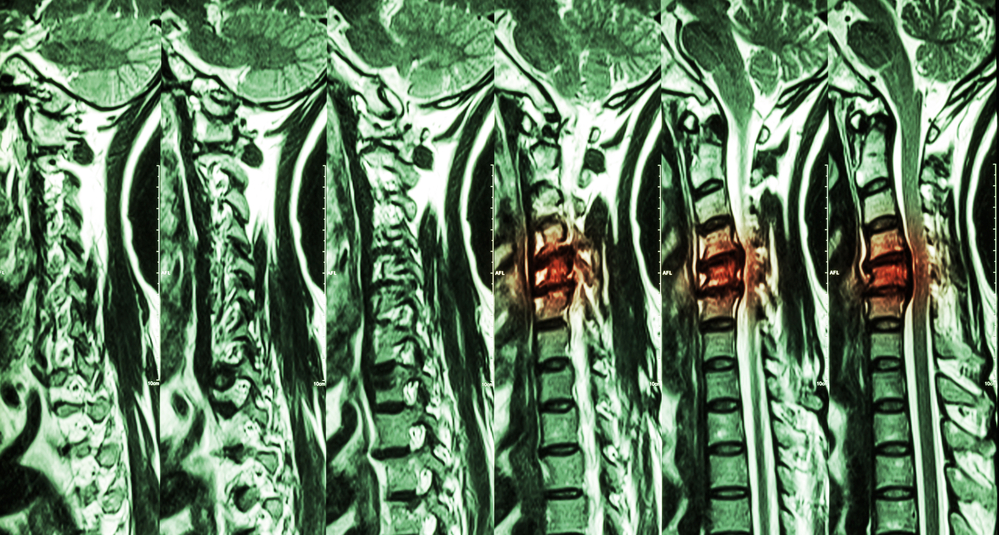

Cervical Spondylosis With Disc Herniation ( MRI Of Cervical Spine Ayurveda Treatment Of Cervical Spine  Manyasthambha is one of the eighty. Sleeping properly and eating freshly cooked food by improving lifestyle can help to improve the condition.   ayurvedic remedies like emblica officinalis, shunthi or ginger, and gambhari used to treat cervical spondylosis.  for treating cervical spondylosis, ayurvedic treatment includes the following: Since ayurvedic treatments not only give you relief from cervical spondylosis but. Ayurveda Treatment Of Cervical Spine.